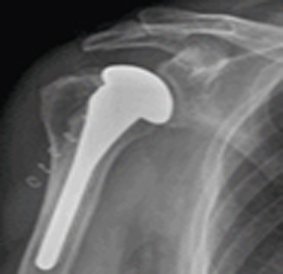

어깨 역행성 인공관절수술

둥근 상완골 끝에는 오목한 소켓 모양의 인공관절 부품을, 오목한 부위에는 볼록한 공 모양의 인공관절 부품을 사용하여 삼각근을 이용해 팔을 들어올릴 수 있게끔 치료를 시행하게 됩니다.

역행성인공관절(수술후)